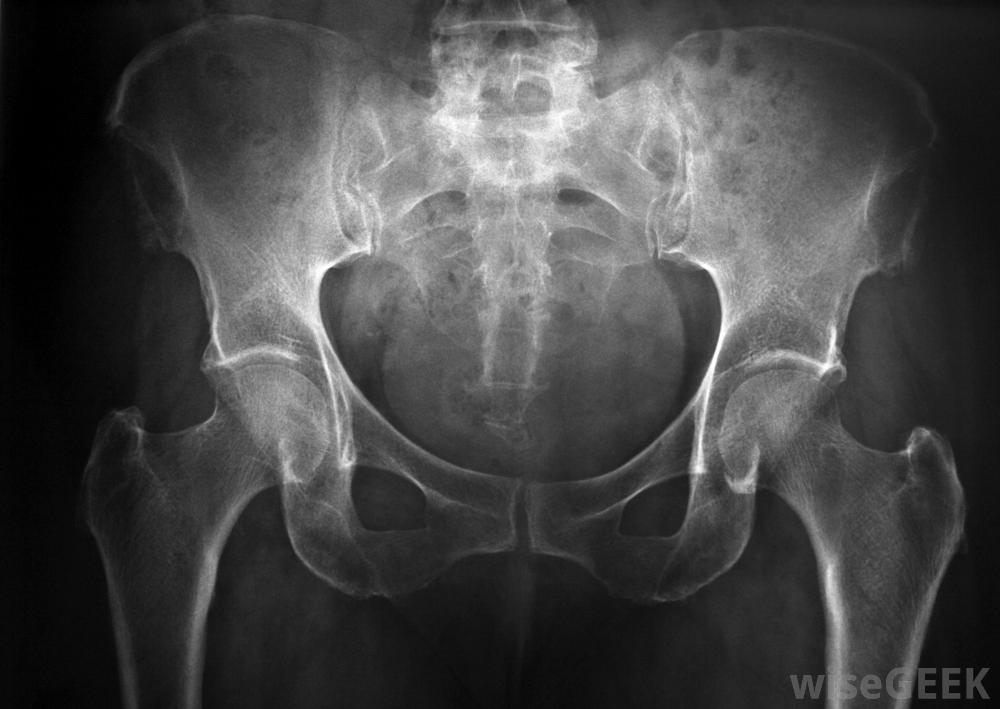

X光可用于寻找与盆底功能障碍相关的问题。盆底功能障碍的症状可能因协调问题的程度和特定肌肉的不同而有所不同涉及。许多人排便困难,导致慢性便秘和频繁但无效果的排尿冲动。当肌肉异常虚弱时,便是主要问题。女性在性交过程中也可能经历严重疼痛,因为支撑阴道的肌肉无法放松正确。

盆底功能障碍会导致排尿、排便和性交困难医生通常可以根据病人的症状和全面的体格检查来诊断盆底功能障碍。可以进行X光片和其他影像扫描,以寻找前列腺肿大、器官脱垂或肌肉缺损的迹象。医生可以按压下腹部,看看是否有压迫感,以及有些情况下,可以用摄像机探头观察肠道或阴道内的肌肉运动